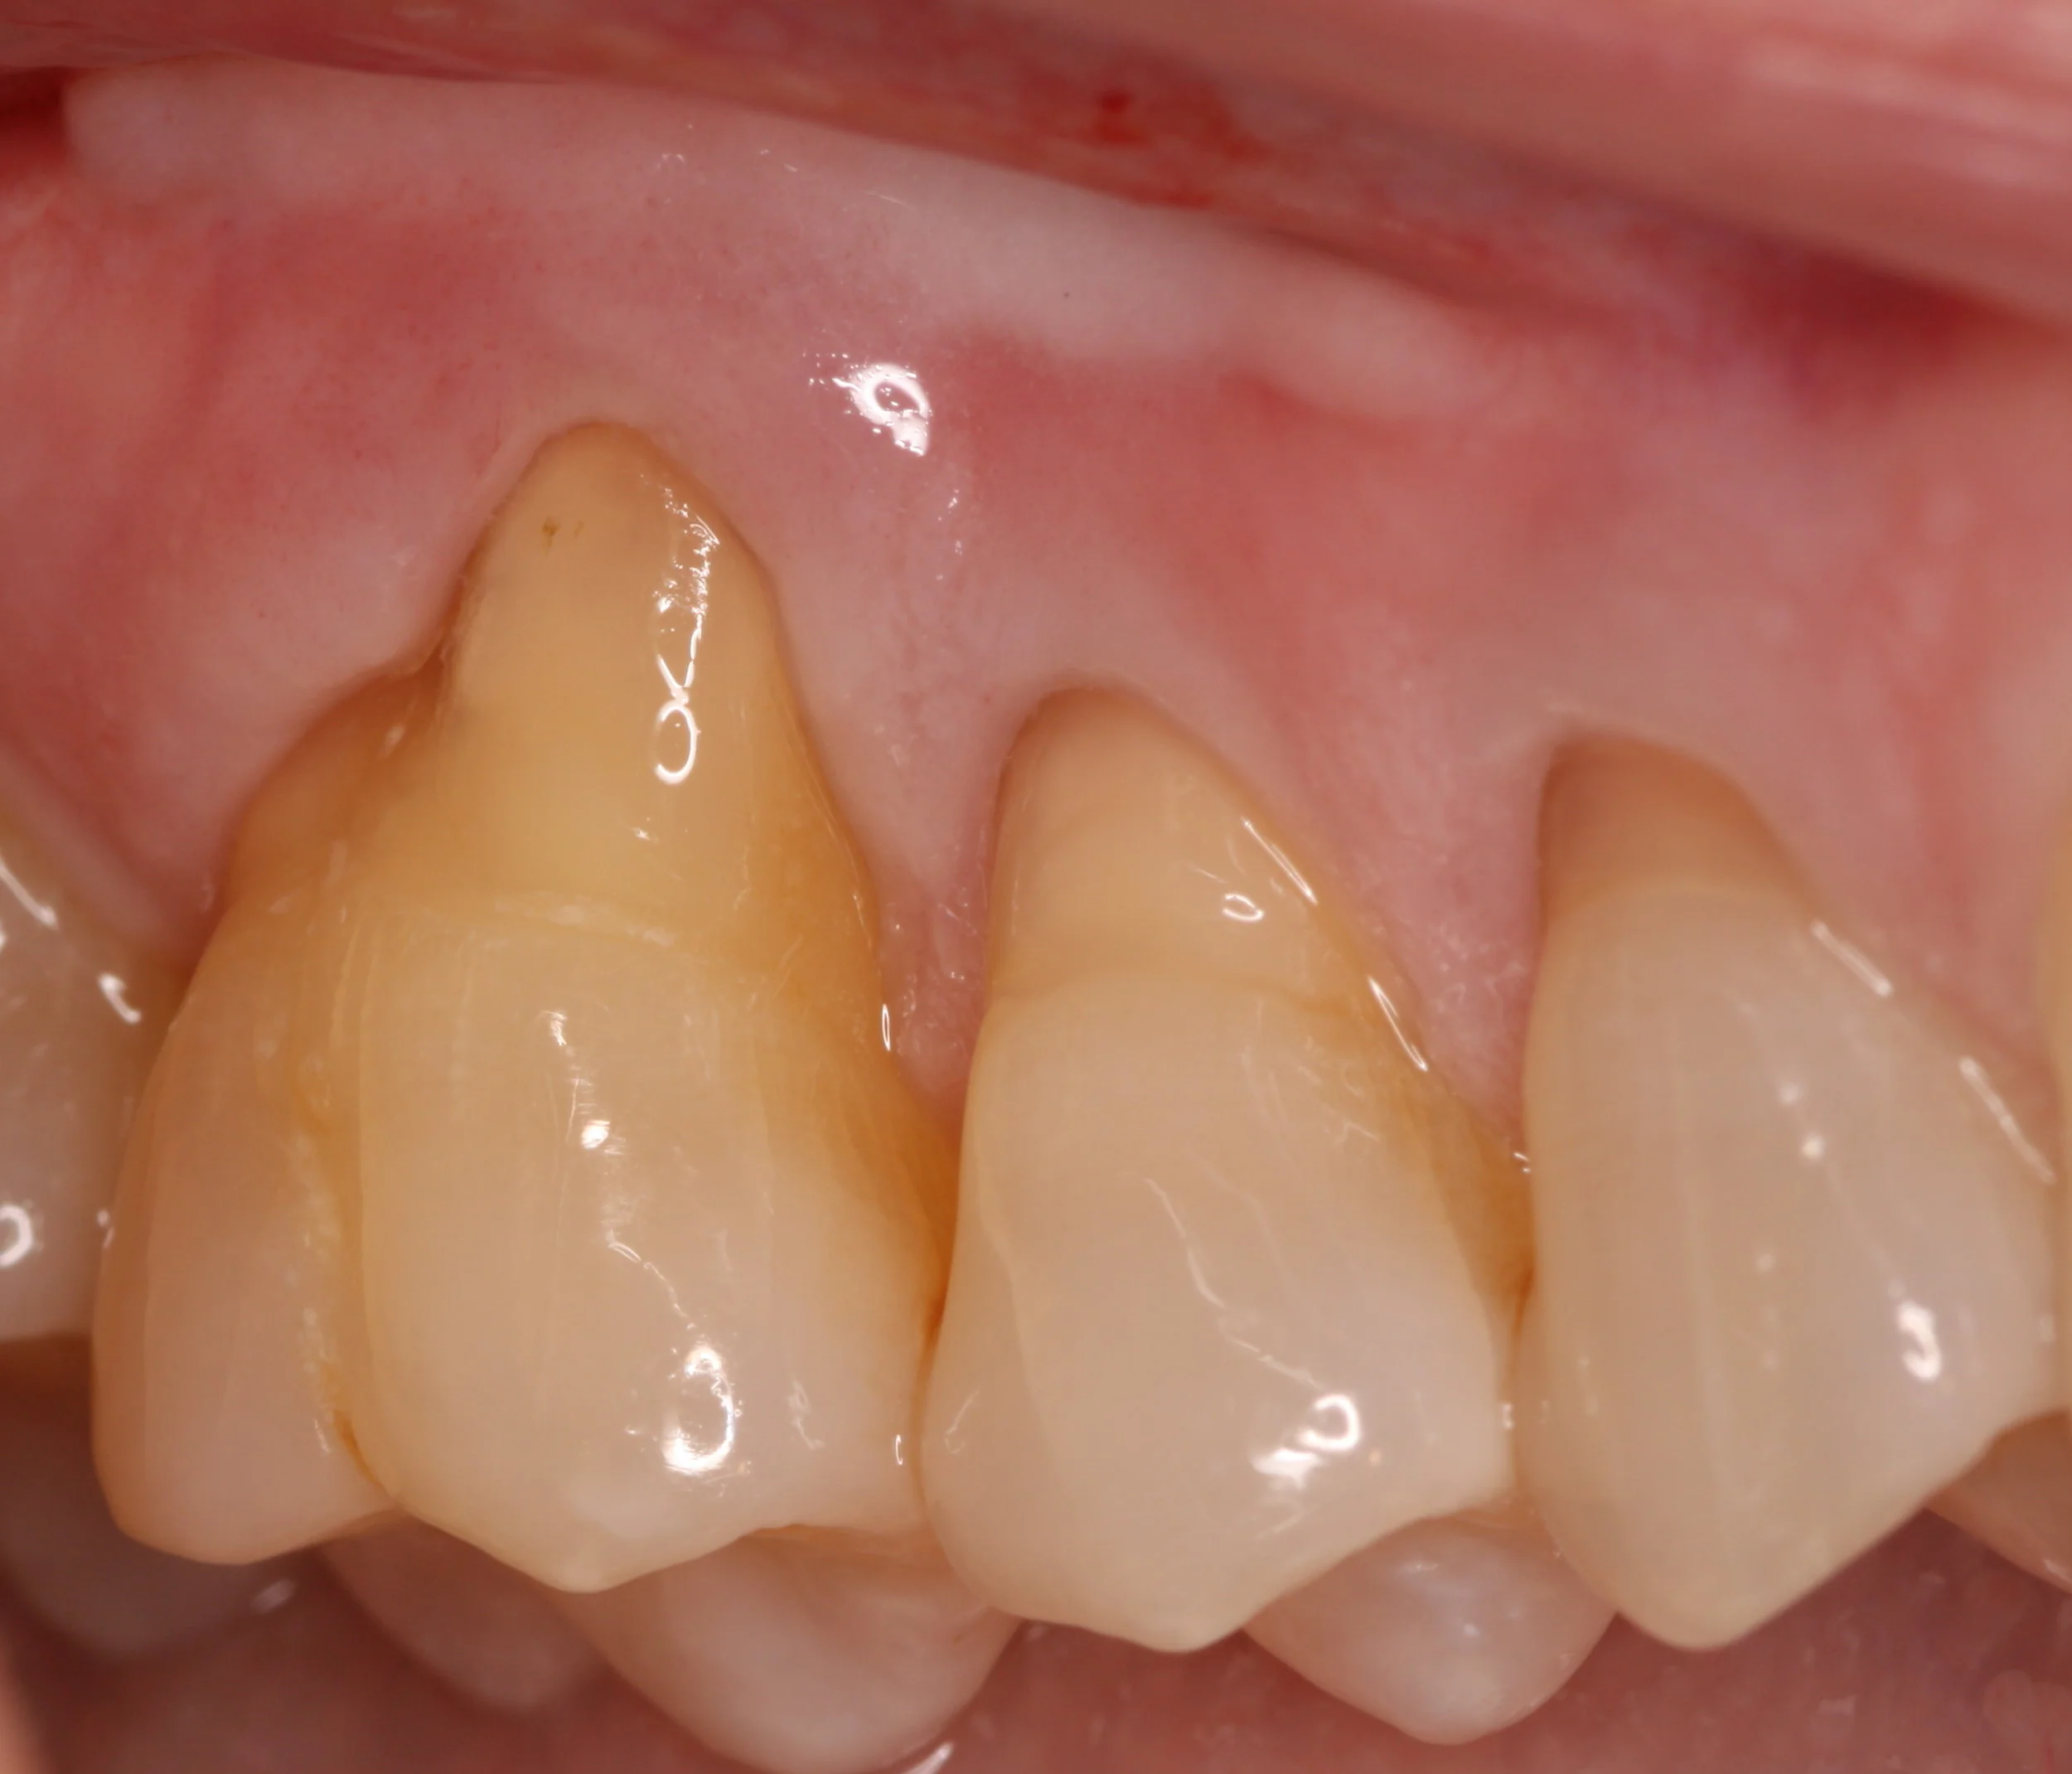

Tooth sensitivity has several causes, including decay and trauma. However, the focus of this post is the type of tooth sensitivity I most often see: tooth sensitivity associated with exposed dentin. In this case, it is also referred to as dentin hypersensitivity. As you may recall from the 1st post, dentin is comprised of microscopic tunnels called dentinal tubules that extend from the pulp at the core of the tooth out to the dentin surface. These tubules are filled with fluid and also contain cellular processes (arm-like extensions of tooth cells that reside in the pulp).

What Causes Exposed Dentin?

Dentin becomes exposed due to a variety of processes involving gingival recession or loss of enamel associated with any (or a combination) of the following: